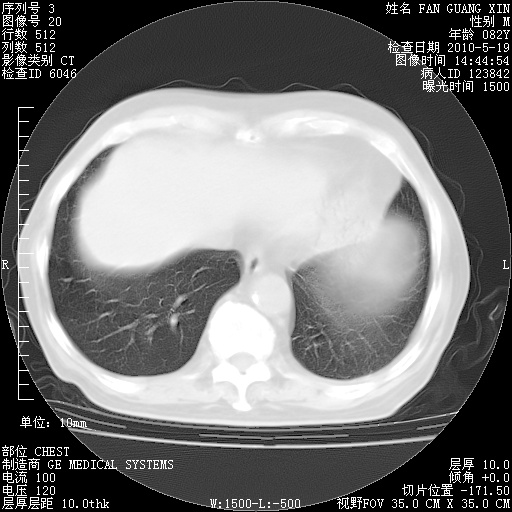

治疗3周后的肺部CT

治疗3周后的肺部CT纵隔窗